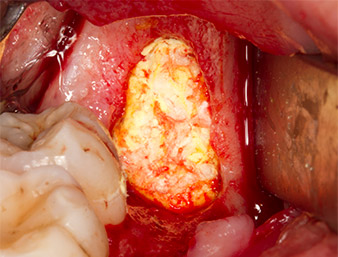

Con el fin de obtener material autógeno para el tratamiento posterior de la herida, se utilizó un inserto piezoquirúrgico (Piezomed B5) para obtener virutas de hueso sano del entorno del resto radicular (figura 5).

El tejido autógeno se extrajo con la punta de trabajo en forma de pala del inserto y se guardó en solución salina fisiológica hasta su posterior utilización (véase figura 13).